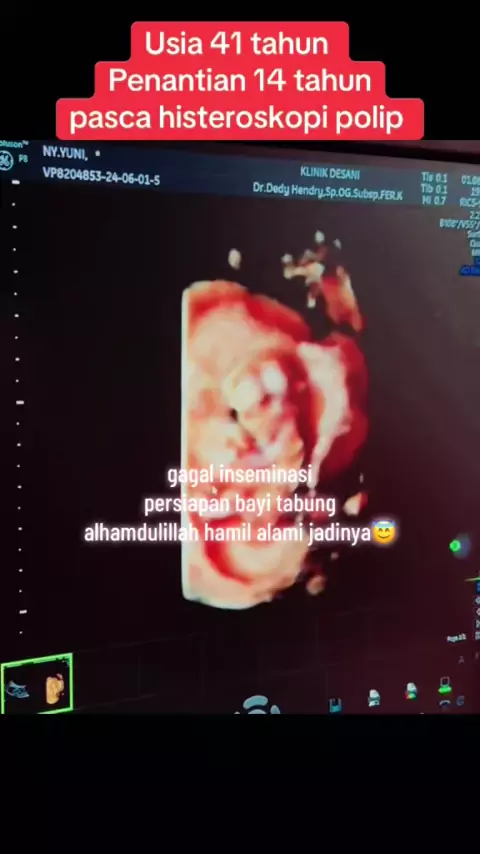

Alhamdulillah Penantian “15 tahun” untuk hari ini 4-4-24 dengan kasus kista endometriosis dan adenomiosis yang sudah dilakukan laparoskopi-histeroskopi dan inseminasi kemudian lanjut bayi tabubg dengan cadangan telur yang sangat menurun dan hanya dapat 1 embrio blastokist saja.. Alhamdulillah dengan ultra long protocol FET menempel dan hamil sehat sampai lahiran… semua terjadi atas ijin dan rahmat Allah SWT yang maha berkuasa dan berkehendak atas segala sesuatu.. Alhamdulillah ya Allah #ivf #iv...